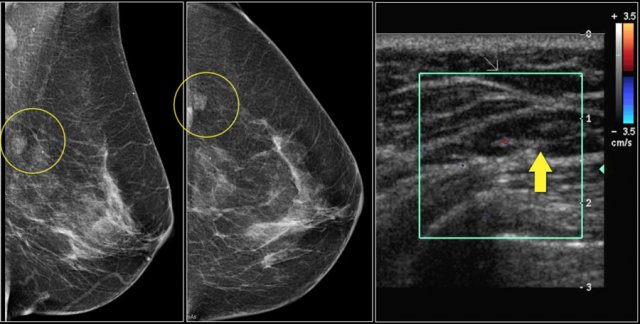

Notice the distortion of the normal breast architecture on oblique view (yellow circle) and magnification view.

A resection was performed and only scar tissue was found in the specimen.

This patient presented with a mass on the mammogram at screening, which was assigned as BI-RADS 0 (needs additional imaging evaluation).

Additional ultrasound demonstrated that the mass was caused by an intramammary lymph node.

The final assessment is BI-RADS 2 (benign finding).

Don't forget to mention in the report that the lymph node on US corresponds with the noncalcified mass on mammography.

In the paragraph on location we will discuss how we can be sure that the lymph node that we found with ultrasound is indeed the same as the mammographic mass.